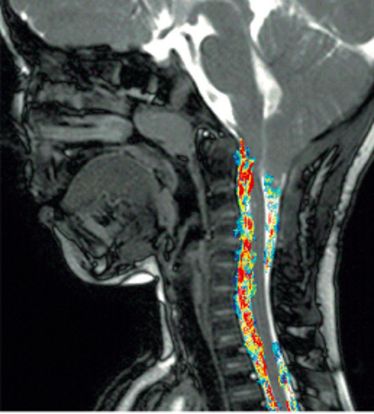

Gastvortrag PD Dr. Mike Wattjes (Amsterdam): New MRI aspects of MS pathology: Does grey matter?

Gastvortrag PD Dr. Mike Wattjes (Amsterdam): New MRI aspects of MS pathology: Does grey matter?